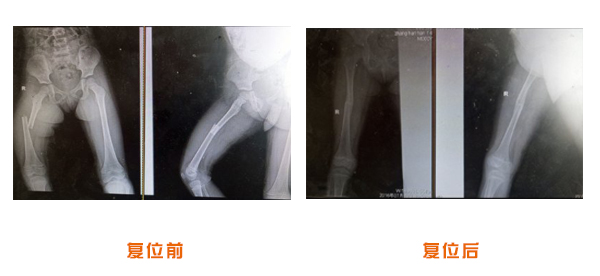

肥城市安駕莊梁氏骨科醫(yī)院是一所以梁氏手法正骨配合膏藥為特色的現(xiàn)代化專科醫(yī)院。

梁氏骨科術(shù)始創(chuàng)于清雍正年間,歷經(jīng)八代,至今已有三百年歷史。據(jù)1929年泰安縣志載“梁瑞圖先生,字增生,號(hào)蓮峰,安駕莊人,精岐黃并發(fā)明接骨,凡跌打車凡跌打車軋皮不破而碎骨者......【詳細(xì)】 |